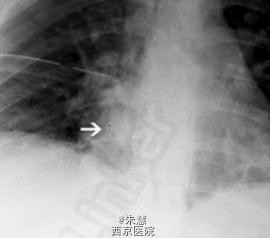

患者女,16岁,因气管异物转入。入院4天前,患儿吸入订书钉。

胸片显示订书钉位于右主支气管内。